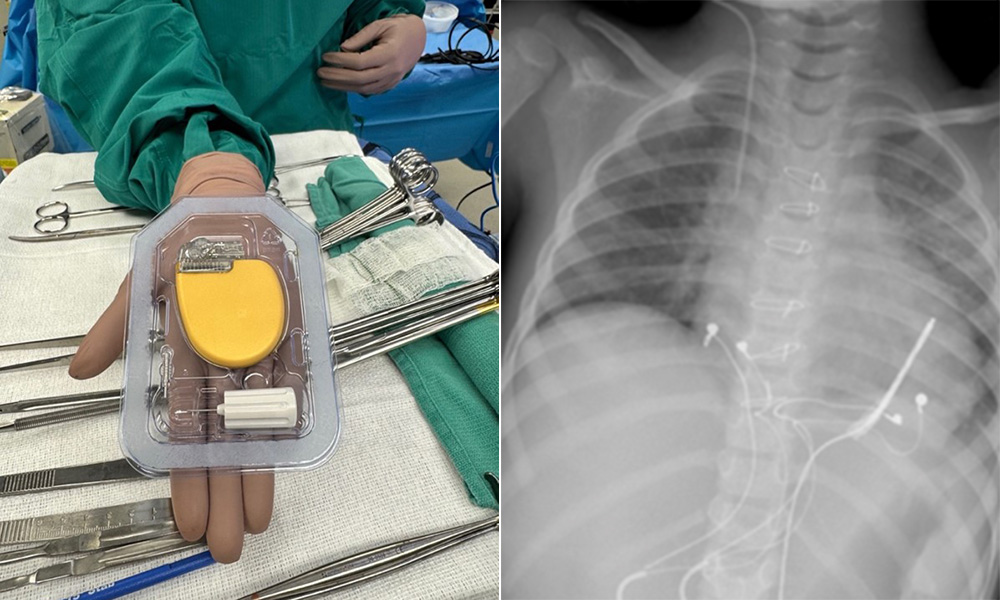

Norton Heart & Vascular Institute joins landmark clinical trial testing pacing therapy for HFpEF heart failure patients